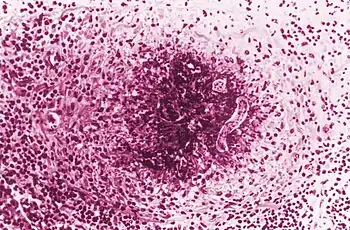

Photomicrograph revealed histopathologic features contained within a sample of human lung tissue, which had been caused by the dog roundworm, Toxocara canis, in a case of toxocariasis